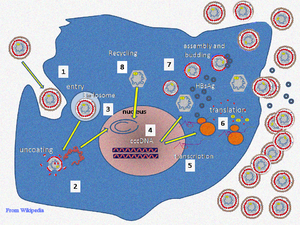

التناسخ

دورة حياة ڤيروس التهاب الكبد البائي معقدة. التهاب الكبد البائي هي واحدة من عدد قليل من الڤيروسات المعروفة غير القهقرية والتي تستخدم النسخ العكسي للڤيروسات كجزء من عملية المضاعفة. ويستطيع الڤيروس دخول الخلية بالارتباط بمستقبلات مجهولة على سطح الخلية ويدخل إليها بالامتصاص. وحيث أن الڤيروس يتكاثر عن طريق الحمض النووى R المفرز من انزيمات الُمضيف، يجب نقل الحمض النووي الجينومي للڤيروس إلى نواة الخلية عن طريق بروتينات المضيف تسمى المرافقون. ثم يتحول الحمض النووي الڤيروسي الثنائى جزئيا إلى مزدوج كامل ويتحول إلى حمض نووى تساهمي دائري مغلق(cccDNA) والذي يعد كنموذج للنسخ من أربعة الحمض النووى الڤيروسى mRNAs. وتستخدم أكبر mRNA، (والذي هو أطول من الجينوم الڤيروسي)، لصنع نسخ جديدة من الجينوم، ولصنع البروتين الأساسي للغلاف الخارجى وبوليمرايز الحمض النووى الڤيروسى. وتخضغ هذه النسخ الأربعة الڤيروسية لمعالجة إضافية، وتستمر لتكوين نسل الڤيروس التي تنطلق من الخلية أو تعود إلى النواة وإعادة تدويرها لإنتاج المزيد من النسخ.[13][15] ثم تنتقل الحمض النووى الطويل mRNA مرة أخرى إلى السيتوبلازم حيث بروتين الڤيروس P يكون الحمض النووي عن طريق نشاطه عكس الناسخ.